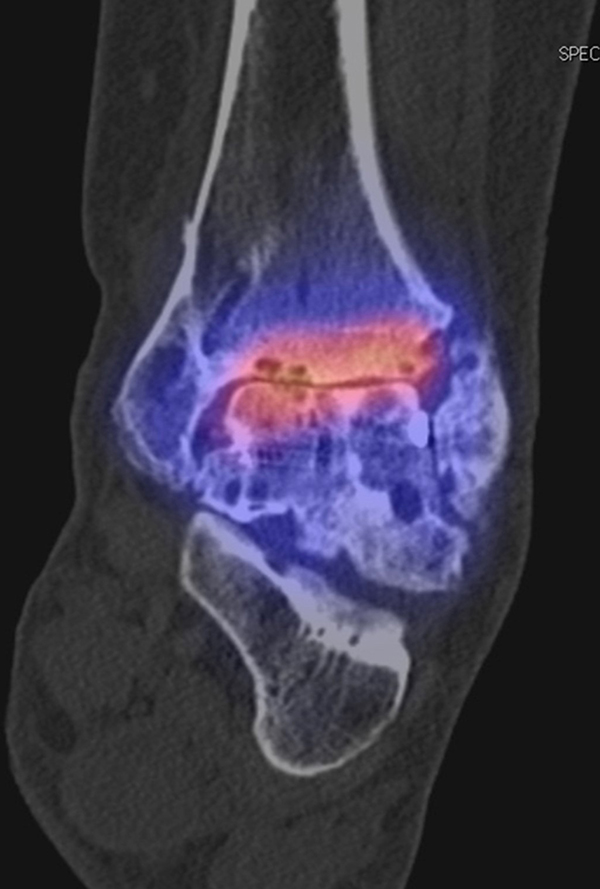

SPECT/CT zur Beurteilung von Endoprothesen

Weltweit nimmt die Prävalenz von Sprunggelenk-Prothesen durch Verbesserungen der Implantate und chirurgischen Techniken zu. Trotzdem berichtet ein signifikanter Anteil von Patienten über persistierende Beschwerden nach Prothesen-Implantation, sodass in der Literatur über Revisionsraten in bis zu 39 % der Fälle berichtet wird 5051. Die Ermittlung der Schmerzquelle mit den konventionellen bildgebenden Verfahren (Röntgen, CT, MRT (auch mit Metall-Artefakt-Reduktion)) ist begrenzt, so dass hier die SPECT/CT die Aussagekraft ähnlich wie bei der Beurteilung anderer Prothesen (z. B. Knie und Hüfte) signifikant erhöht. Verschiedenste Fragestellungen müssen bei der Evaluation einer schmerzhaften Sprunggelenk-Prothese beantwortet werden: Achsenstellung, Prothesenlage, Impingement, Lockerung, Senkung von Prothesenkomponenten, Frakturen, Zysten, Osteolysen, Anschlussarthrosen, Infektionen, Nervenschäden, CRPS, Materialunverträglichkeiten.

Zur Zuordnung von Mehrspeicherungen und morphologischen Veränderungen im Bereich von Prothesen eignen sich folgende Kriterien 51:

• Flächiger starker Fokus am Prothesen-Knochen-Interface → V. a. Lockerung

• Fokus medial oder lateral am Prothesen-Knochen-Interface → V. a. fokaler biomechanischer Stress aufgrund von Fehlstellung der Prothese oder des Rückfußes

• Fokus medial oder lateral im Gelenkabschnitt / Zone zwischen Talus und den Malleolen → Ausdruck eines Impingement

• Im CT zart randsklerosierte rundliche Osteolyse(n) am Prothesen-Knochen-Interface mit metabolischem Fokus → V. a. symptomatische Zyste

• Fokale oder flächige Mehranreicherungen in angrenzenden Gelenken in Verbindung mit arthrotischen Veränderungen im CT → V. a. symptomatische Arthrose

Beispiele für SPECT/CT-Untersuchungen nach OSG-TEP sind in den Abbildungen 6.1. bis 6.3. abgebildet.